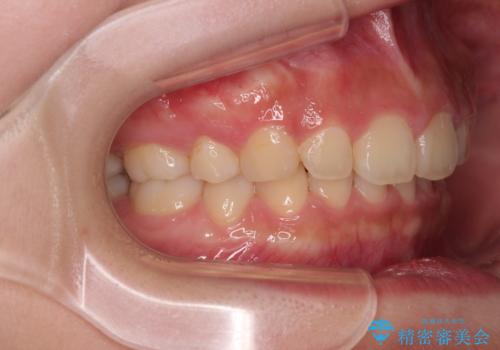

- 飛び出した上顎前歯と、閉じにくい唇、口元の突出した印象の横顔を気にして来院された患者様です。

骨格的な上顎前突であり、上下前歯の前後的な距離が大きいため、上顎は左右第一小臼歯を、下顎は左右第二小臼歯をそれぞれ2本抜歯することで前歯が接触するようにし、さらには奥歯の咬み合わせも、より理想的な状態へ近づけていくこととしました。

3年以上はかかる難症例であるため、表側のワイヤー装置にて治療を行うこととしました。

事前の予想通り、長期間を要する治療となりましたが、横顔の印象が劇的に変化し、患者様には大変満足していただきました。